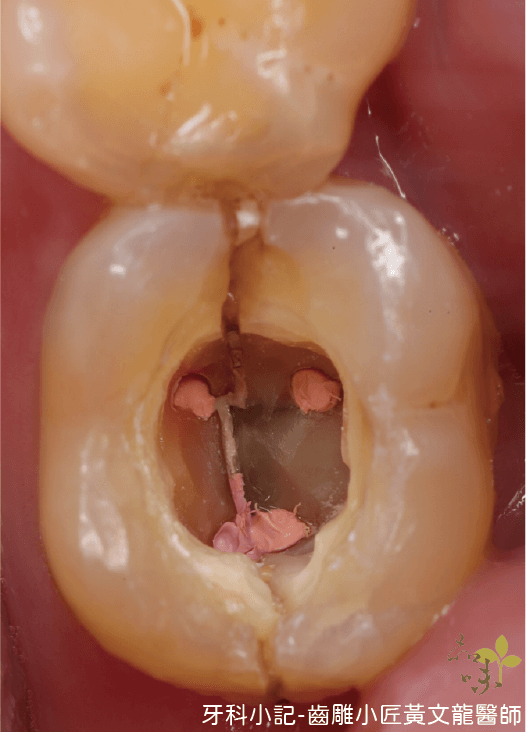

二、牙齒咬頭斷裂 (Fractured cusp)

敘述:牙齒由咬合面往牙齦方向的咬頭斷裂。

症狀:初期可能沒有症狀,也可能伴隨牙髓症狀,像喝冰水敏感、咬東西敏感或疼痛,放久則可能出現牙髓壞死,根尖周圍炎甚至跑出膿包。

處置:需要先確認牙髓狀態,可逆性牙髓炎可以用活髓治療保留牙齒活性,或者是贋復物覆蓋恢復牙齒功能及強度。而如果是不可逆牙髓炎或是牙髓壞死,則需要根管治療並且採贋復物(牙套)恢復牙齒功能及強度。

品味牙醫黃文龍醫師提供

延伸閱讀:為何根管治療後要裝假牙牙套?